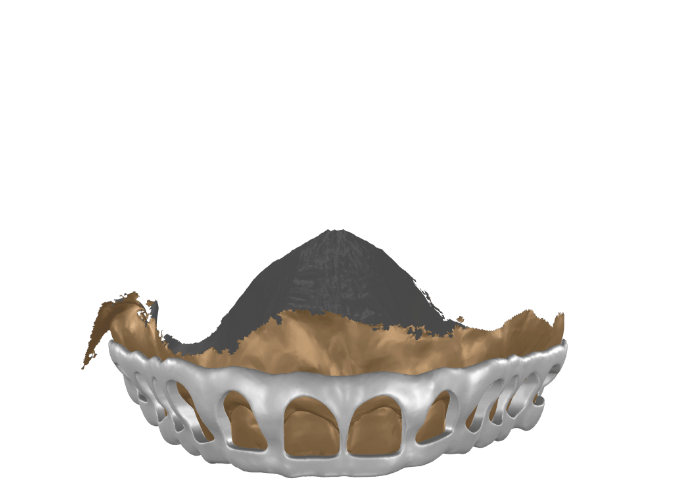

Blueprint

adds creative depth to your work

It lets you bring in scan data, CBCT, and motion

allowing you to extend your smile design into 3D.

It supports interdisciplinary spatial thinking and clear visual communication with your patient.

allowing you to extend your smile design into 3D.

It supports interdisciplinary spatial thinking and clear visual communication with your patient.

This technology is protected by Patent: NL 2037626